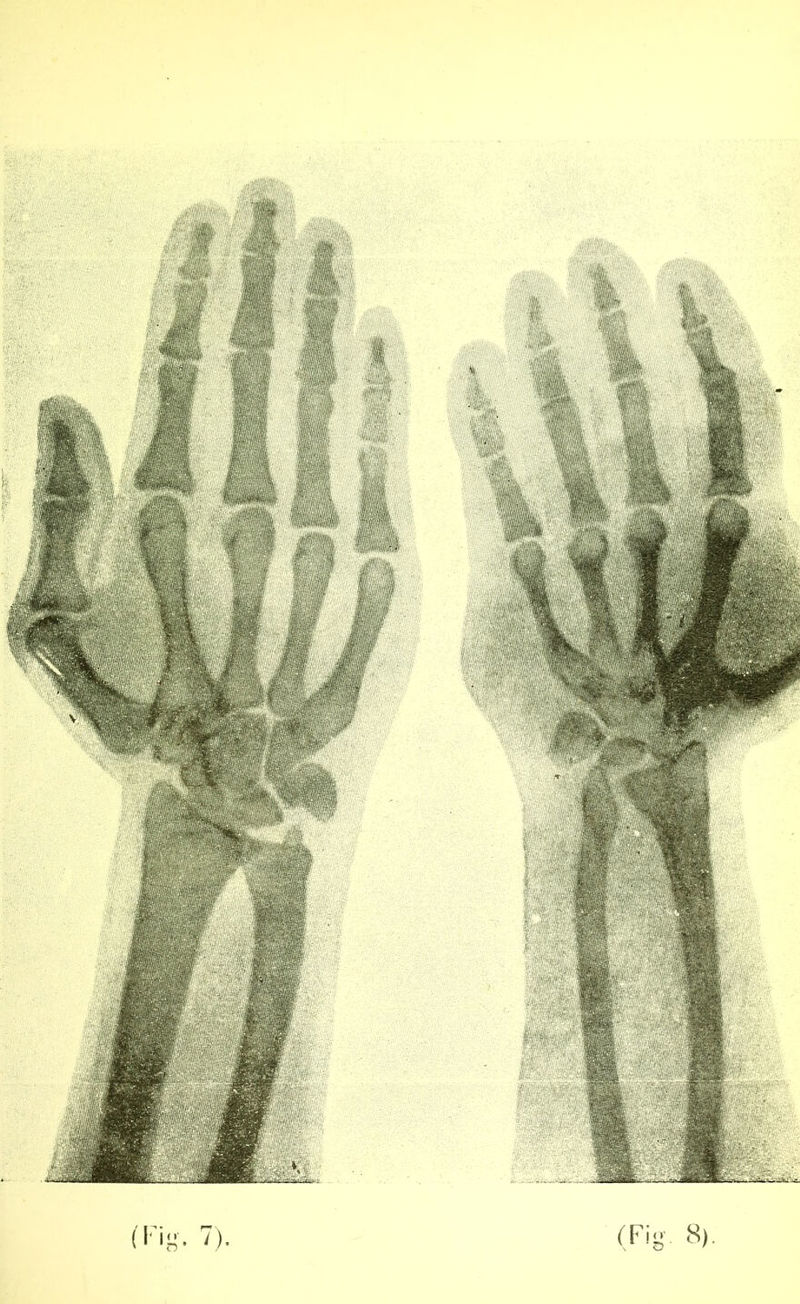

Trois cas de phlébectasie congénitale de l'extrémité supérieure / par Alexandre Pacha Kambouroglou.

Credit: Trois cas de phlébectasie congénitale de l'extrémité supérieure / par Alexandre Pacha Kambouroglou. Source: Wellcome Collection.